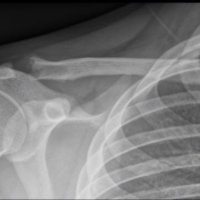

AC joint separation, often called a shoulder separation, is a dislocation of the clavicle from the acromion, with disruption of the acromioclavicular ligaments and/or coracoclavicular (CC) ligaments.

This injury is usually caused by a blow to the shoulder, or a fall in which the individual lands directly on the shoulder or an outstretched arm.

Treatment is immobilzation or surgical reconstruction depending on the degree of separation and ligament injury.

Rockwood Classification:

X-Ray Findings